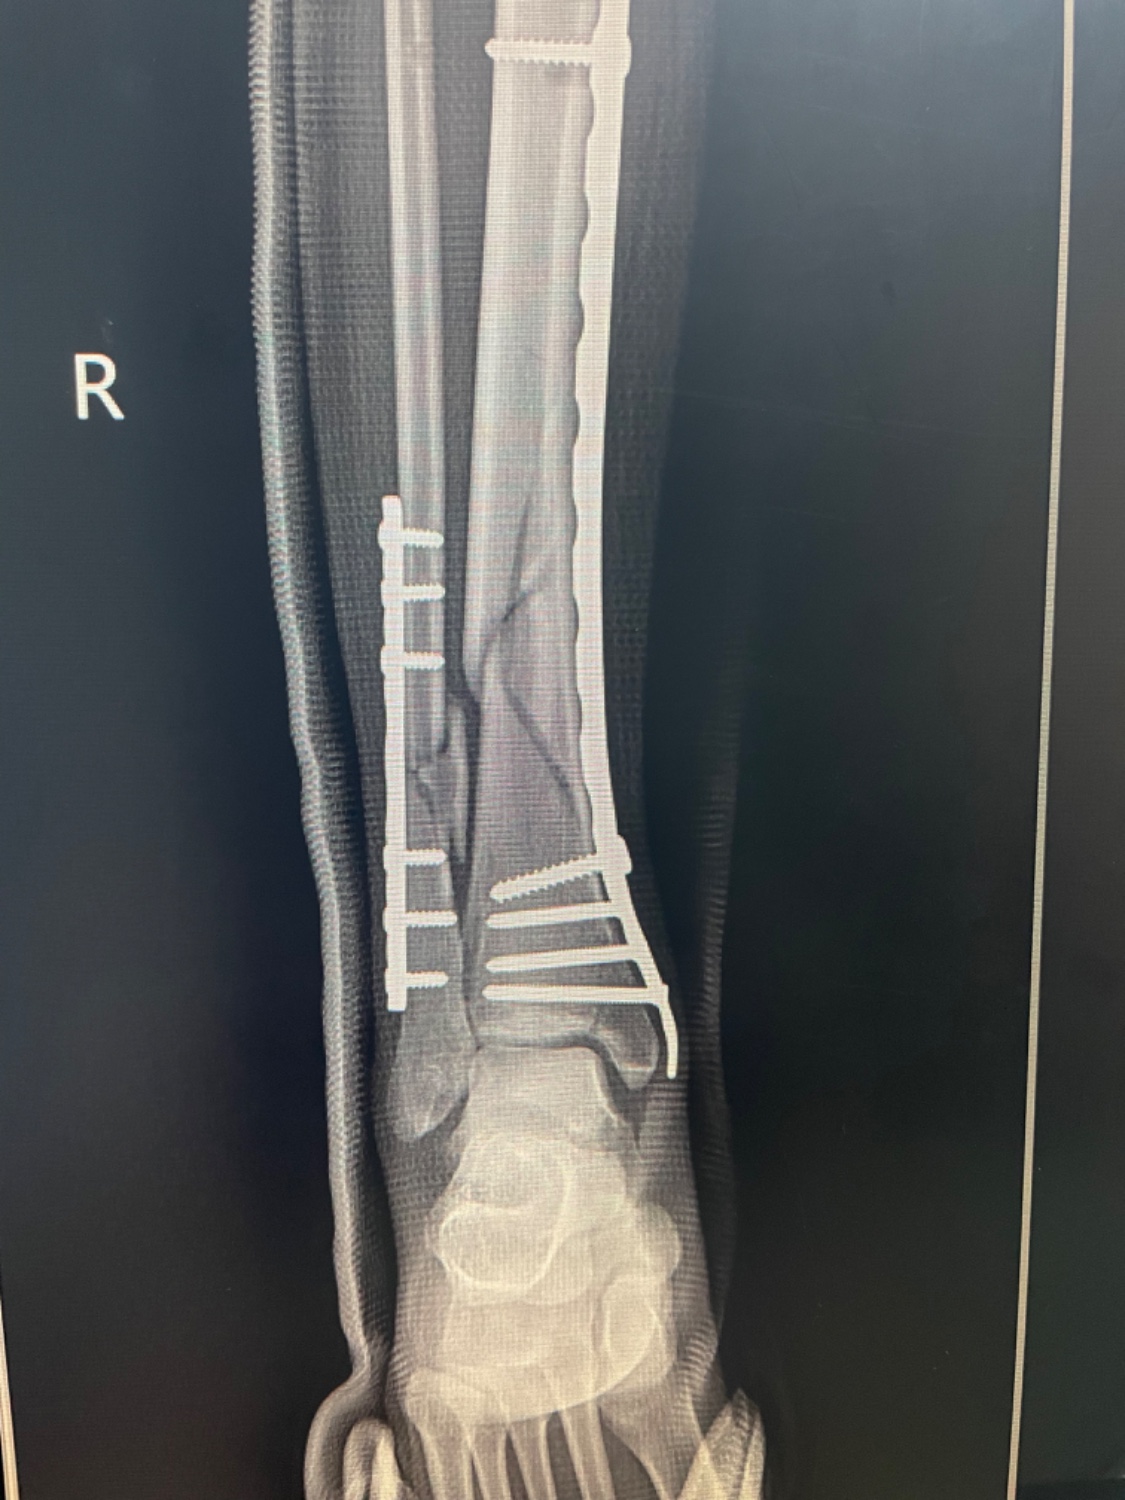

กระดูกหักแบบนี้จะกลับมาเดินปกติมั้ยคะ

ตอนนี้หมอไห่ลงน้ำหนักได้นิดหน่อย แต่ตอนนี้มีอาการข้อติดค่ะแล้วก็ขาเล็กลง อยากทราบว่าจะกลับมาเหมือนเดิมไหมคะ